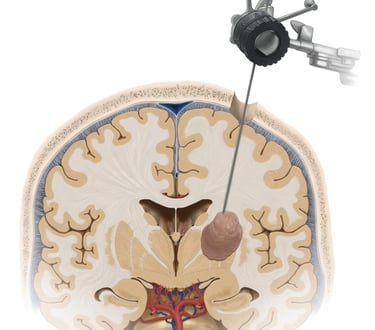

Tumores cerebrales y espinales

Biopsias cerebrales